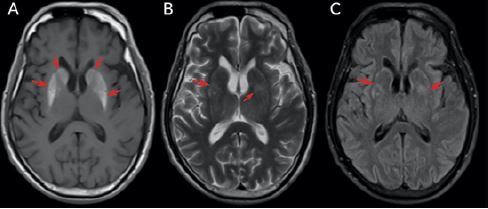

En el ingreso persistía el síndrome clínico, que no se había modificado desde su comienzo. En la inspección general lucía crónicamente enfermo. En los signos vitales tenía presión arterial en 120/60 mmHg, frecuencia cardiaca de 74 latidos por minuto y frecuencia respiratoria de 18 respiraciones por minuto. Los exámenes paraclínicos institucionales aportaron función hepática y renal, vitamina B12, electrolitos, vitamina D, hemograma completo y proteína C reactiva, que fueron normales. Además, se realizaron estudios infecciosos y autoinmunes, que fueron negativos. La neuroimagen ( figura 1) mostró en los núcleos de la base un aumento de la señal en T1 con realce en el medio de contraste de forma bilateral sobre caudado, putamen y globo pálido de forma simétrica; no restringía la difusión ni la susceptibilidad magnética. Se diagnosticó hemicorea asociada con HC-HN. Adicionalmente, se le realizó una angiorresonancia de cerebro que evidenció cambios por su enfermedad crónica y se apreciaban dos imágenes de aspecto sacular, compatibles con dilataciones aneurismáticas, consideradas un hallazgo incidental.

Adicionalmente, en el caso 1, la RMN mostró lesiones hiperintensas en los ganglios basales bilaterales y la manifestación clínica fue unilateral (hemicorea izquierda). No queda claro cuáles ganglios basales tienen la alteración funcional (derecho o izquierdo) y, por esta razón, no se podría saber si la hemicorea es ipsilateral o contralateral. Pero teniendo en cuenta que lo más común es la presentación contralateral, creemos que en este paciente los ganglios basales derechos tienen mayor afectación funcional.